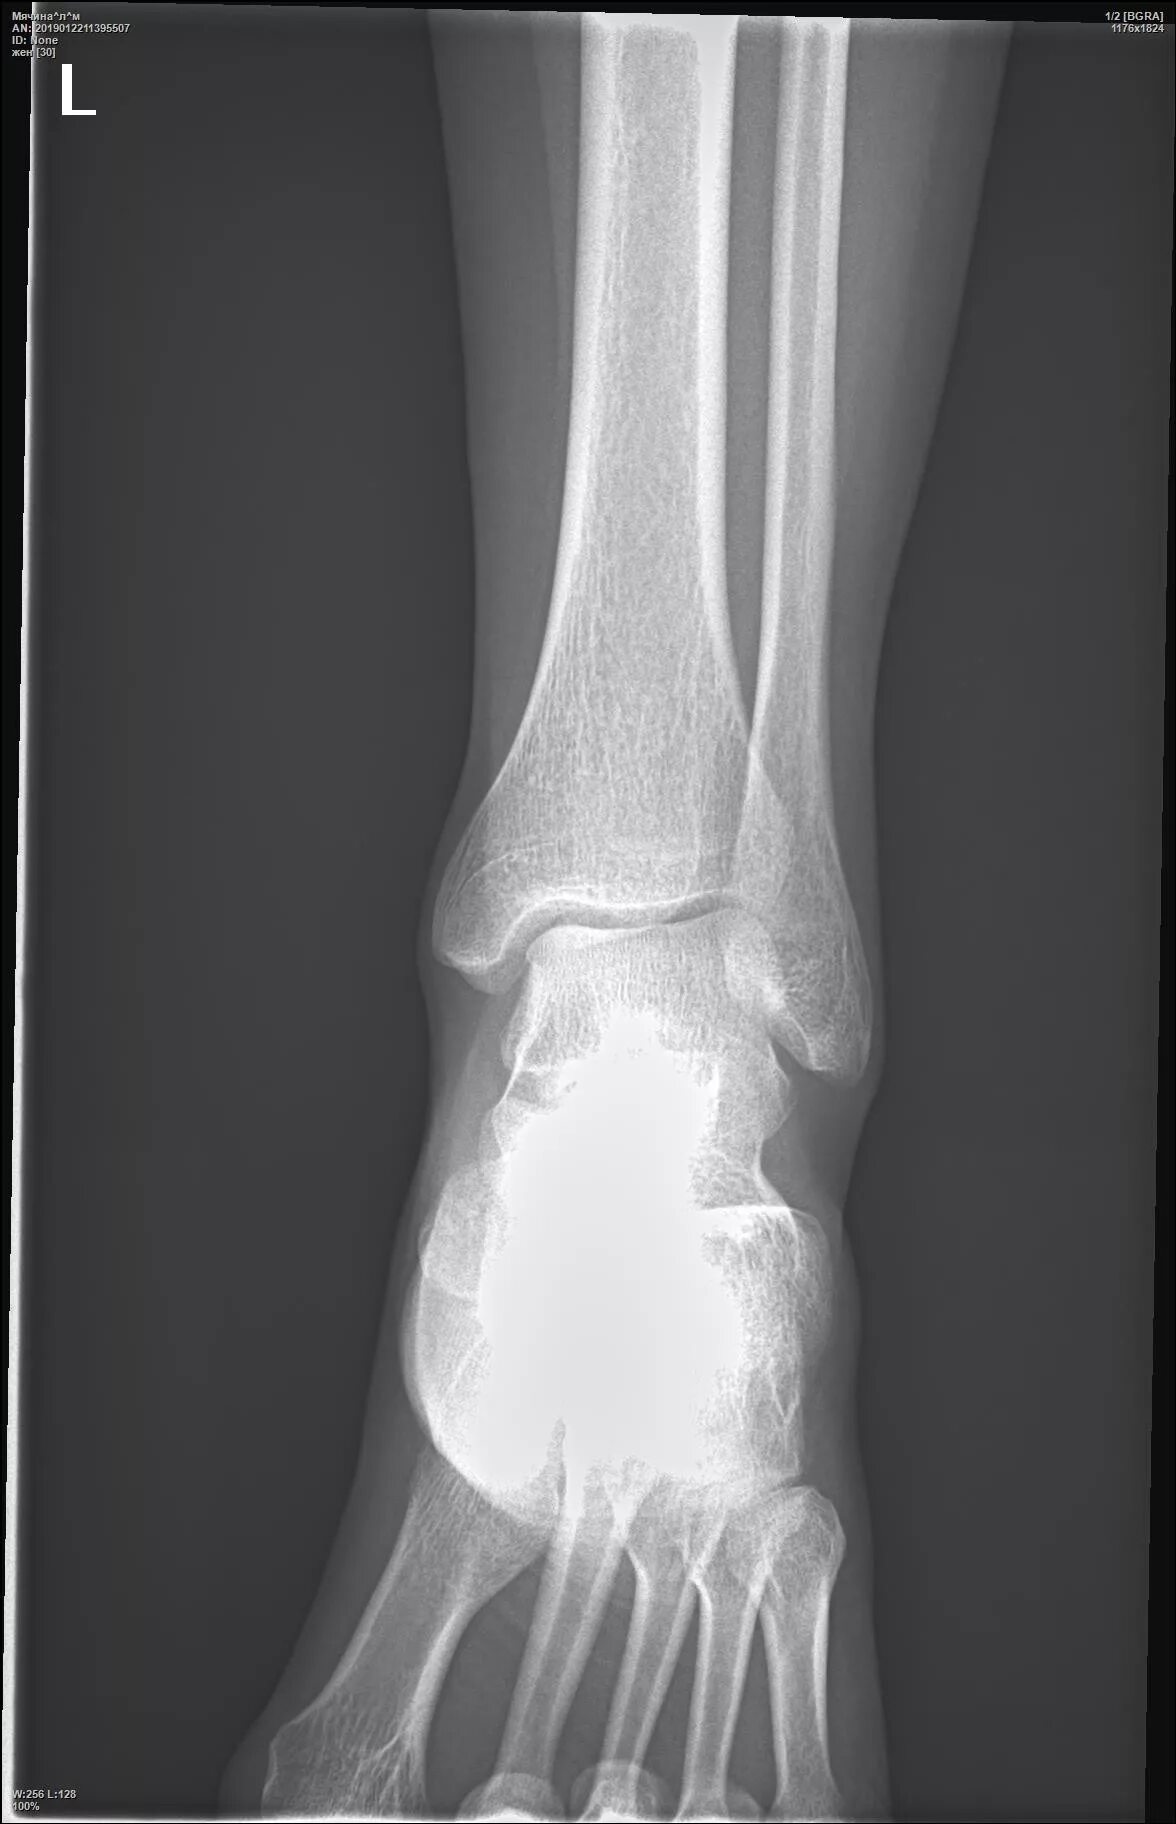

Трещина в кости ноги сколько